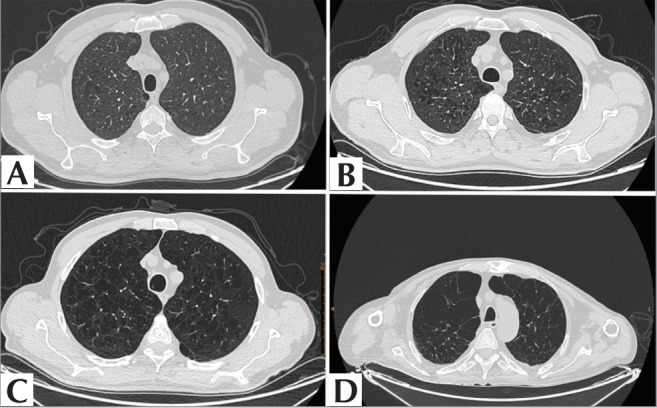

Materials and methods: Over the last 12 months, a total of 354 patients were screened based on the presence of terms such as “Fleischner”, “CLE”, and “centriacinar” in their thoracic CT reports, culminating in a study population of 82 patients. The study population was divided into Group 1 (Fleischner mild and moderate; n= 45) and Group 2 (Fleischner confluent and advanced destructive; n= 37). Volumetric segmentation was performed, focusing on the upper lobe segments of both lungs. From these segmented volumes, radiomics parameters including shape, size, first-order, and second-order features were calculated. The best model parameters were selected based on the Bayesian Information Criterion and further optimized through grid search. The final model was tested using 1000 iterations of bootstrap resampling.